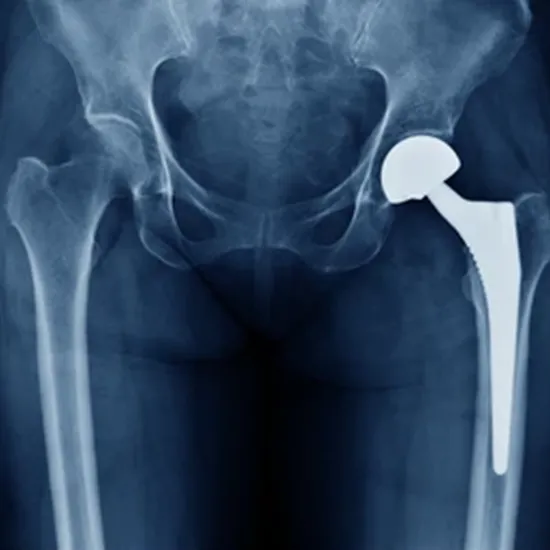

An MRI is a sensitive examination for examining the bones and nearby soft tissues. Many of the causes of both hip joint problems can be evaluated using MRI technology. Hip discomfort can result from a variety of disorders, including abnormalities with the patient's soft tissues and bone structures.

The optimum treatment option must be decided upon after a proper diagnosis. Hip discomfort may be brought on by a torn acetabular labrum, tumors, an infection, or bone necrosis. From a list of potential causes, the scan aids in determining the true cause.

When there is considerable hip stiffness and discomfort, both hip joints are screened using an MRI. There are various potential causes of hip discomfort. The MRI is beneficial for identifying the various sources of hip joint pain. It is useful to identify disorders like bursitis, which can be painful and present in the lateral area of the hip.

The MRI can also spot instances of muscle damage brought on by severe athletic activity.